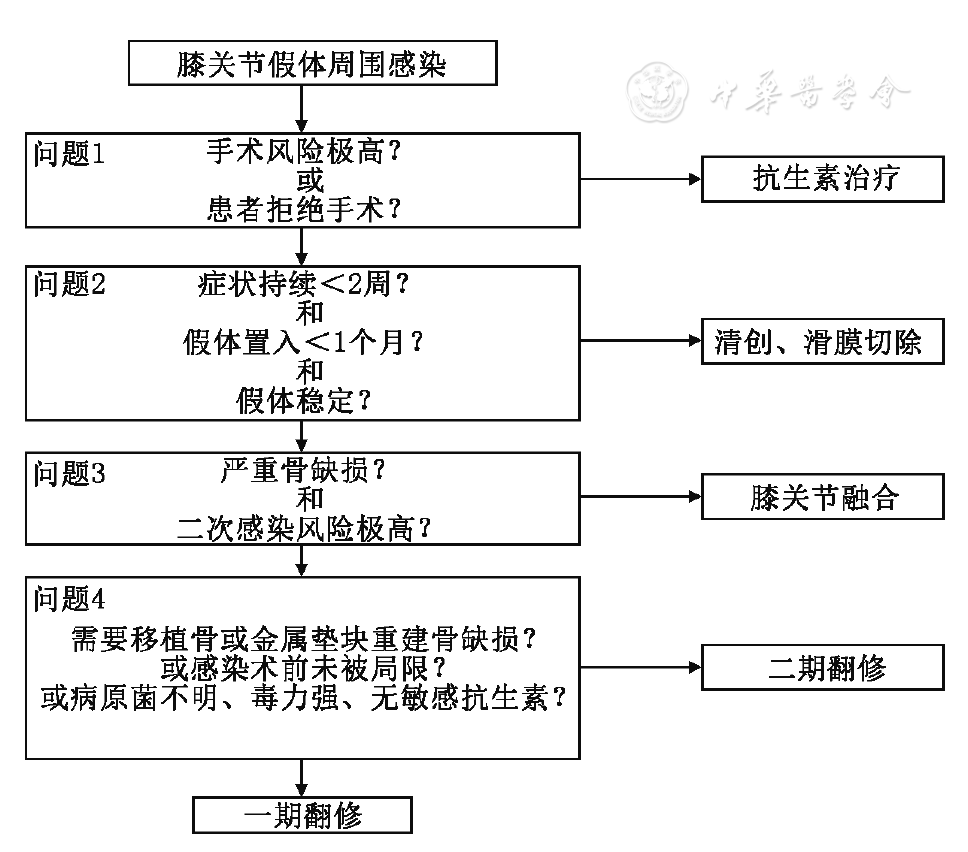

os 全膝关节置换感染的诊断和处理 好医生

一期翻修术治疗全膝关节置换术后假体周围感染的中长期随访结果

保留假体清创术治疗人工关节置换术后假体周围感染的临床研究 中国修复重建外科杂志 唯一官网

一期翻修术治疗全膝关节置换术后假体周围感染的中长期随访结果